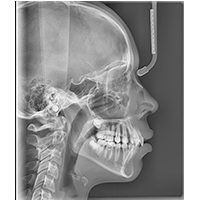

Telerradiografia